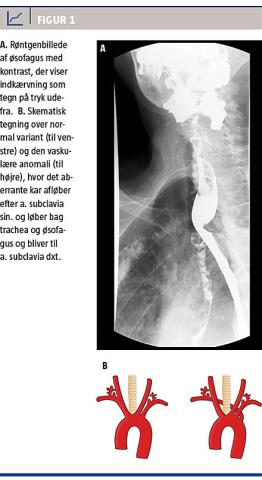

Ved en klinisk undersøgelse inkl. fleksibel laryngoskopi blev der fundet normale forhold. Pga. patientens anamnese var der indikation for endoskopisk udredning med øsofagoskopi og gastroskopi. Hun var pga. sine konkurrerende sygdomme utryg med det diagnostiske tilbud, hvorfor der i stedet blev foretaget en røntgenundersøgelse med kontrast af øsofagus. Her blev der fundet normalt kontrastnedløb til ventriklen, men på niveau med arcus aorta blev der fundet en indkærvning i kontrasten fra venstre side (Figur 1A). Efterfølgende CT af hals/thorax viste en vaskulær anomali med en abnorm afgående a. subclavia dxt., der komprimerede øsofagus, især pga. forkalkninger heri. Denne benigne tilstand, der muligvis kunne forklare patientens symptomer, beroligede hende, og hun ønskede ikke yderligere tiltag. I samråd med hende blev behandlingen en ændring til mere flydende kost og opfølgning via hendes egen læge.

Et aberrant afløb af a. subclavia dxt. (Figur 1B) er den almindeligste form for karanomali [2]. Den findes dog kun hos under 1% af befolkningen, og størstedelen er symptomfrie. Symptomer ses sjældent hos børn og viser sig som hoste og stridor [3], hvorimod der hos voksne oftere findes dysfagi. Dysfagi pga. denne anomali betegnes dysphagia lusoria og skyldes det unormale forløb af a. lusoria, der afgår fra aorta efter a. subclavia sin. Herefter løber den bag sidstnævnte samt trachea og øsofagus for at fortsætte som a. subclavia dxt. Dysfagi kan forværres ved aterosklerose. Ved milde symptomer kan konservativ behandling med kostændring forsøges evt. med tillæg af antirefluksmedicin som protonpumpeinhibitor [4]. Ved invaliderende symptomer kan der med stor succes udføres bypassoperationer [5].